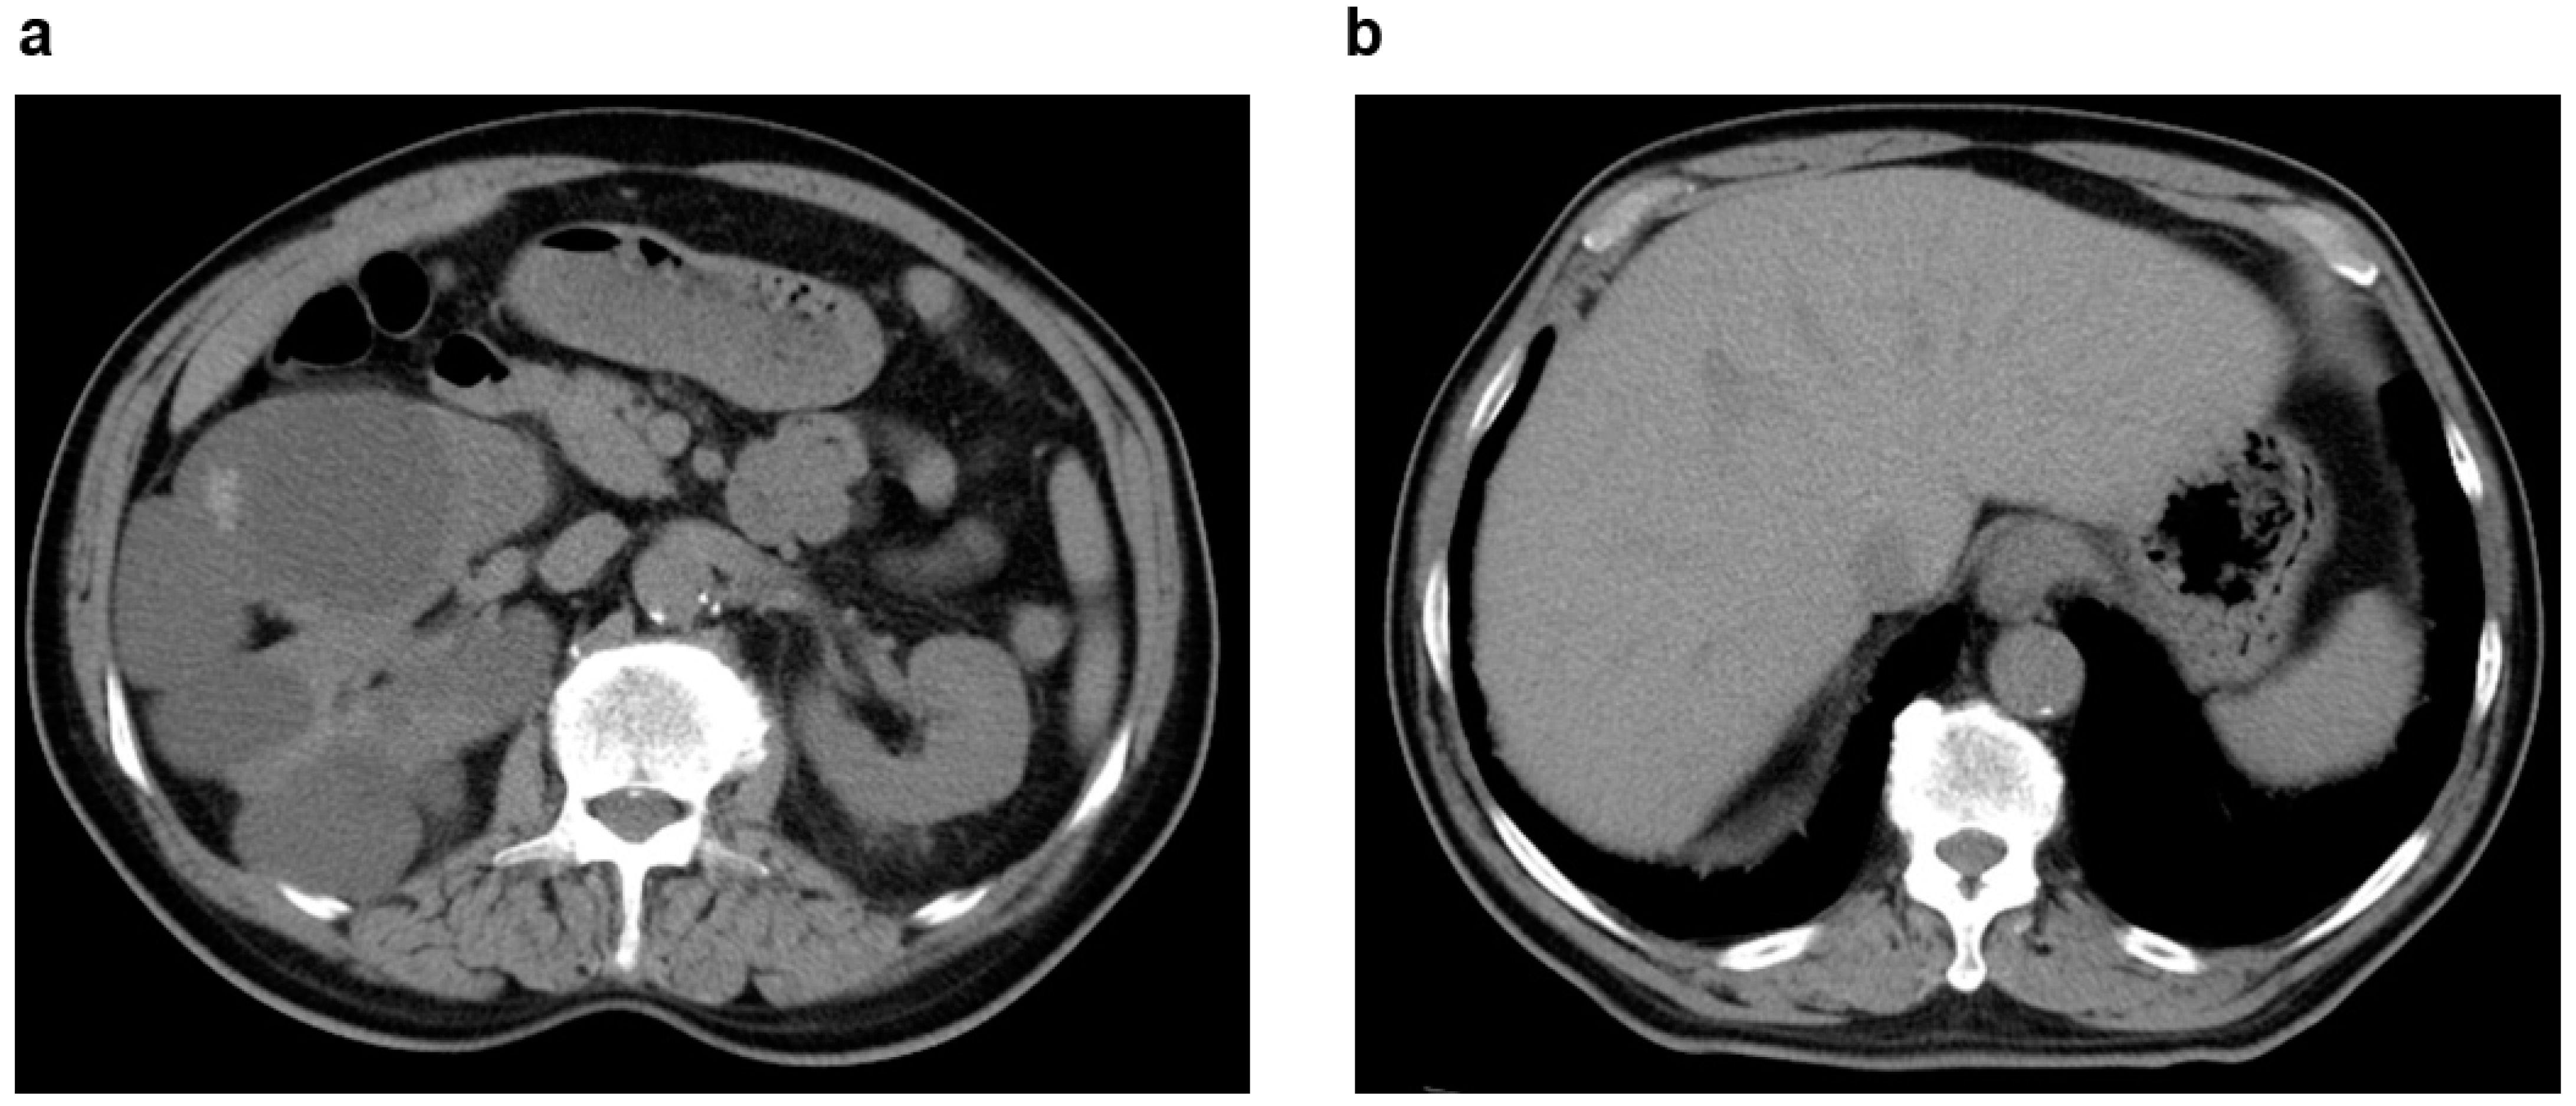

2.5. Unilateral Renal Cystic Disease (URCD)